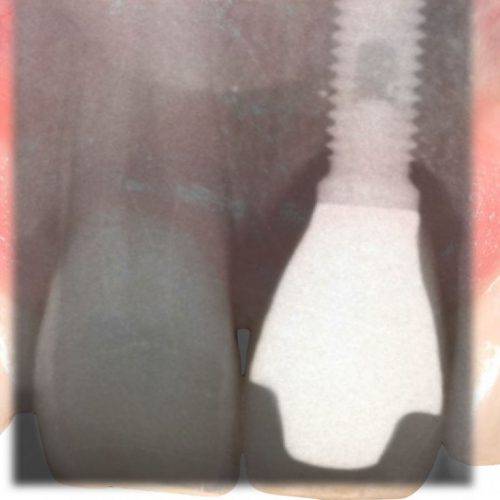

IMPLANTOLOGIA

L’implantologia dentale indica l’insieme di tecniche chirurgiche atte a riabilitare funzionalmente un paziente affetto da edentulismo totale o parziale…